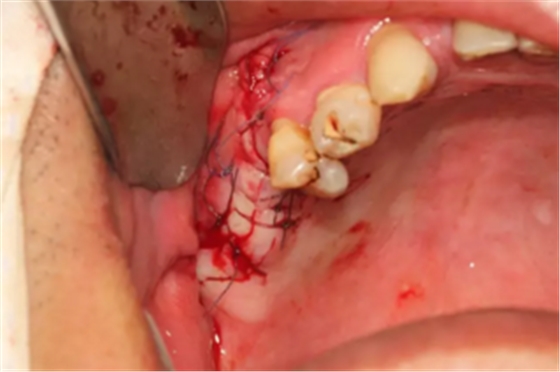

【病例分享】上頜竇大囊腫外提升